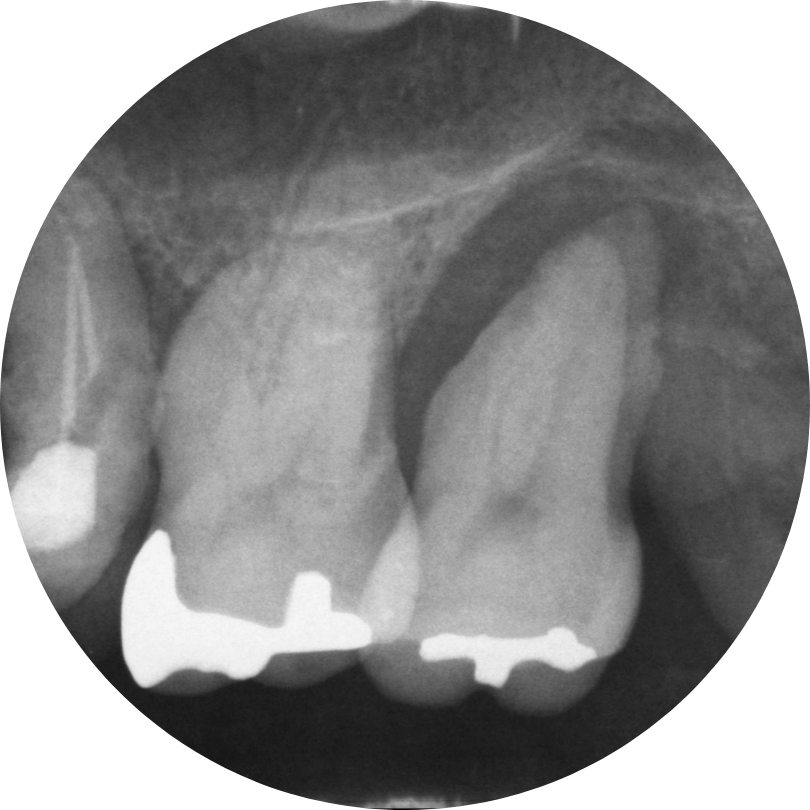

主な歯周病の検査法

レントゲン検査

歯周病の初期段階「歯肉炎」では、歯と歯の間や歯と歯ぐきの境目にプラーク(細菌のかたまり)がたまり、炎症を引き起こします。

その結果、歯肉が腫れ、わずかな刺激でも出血しやすくなります。